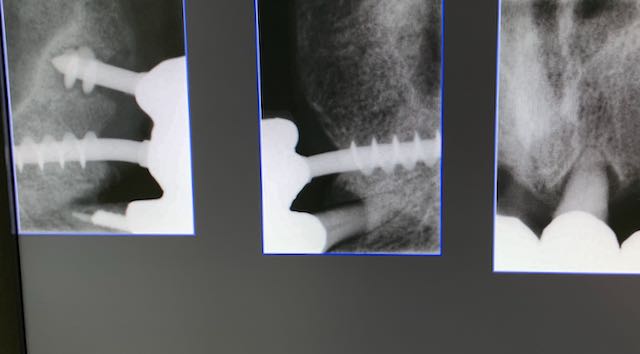

Numero impianti esistenti: 3     Data e numero degli interventi: nel 1993 3 impianti in zona 14  24  25

Tipo di impianto: Tramonte     Numero di impianti inseriti: 2     Saldatura: No    Zona dentale: 21   23

App.Rx Endorale:Vix Win     Tac: No     Situazione estrattiva:  impianti postestrattivi immediati   Densità Secondo Misch: D2